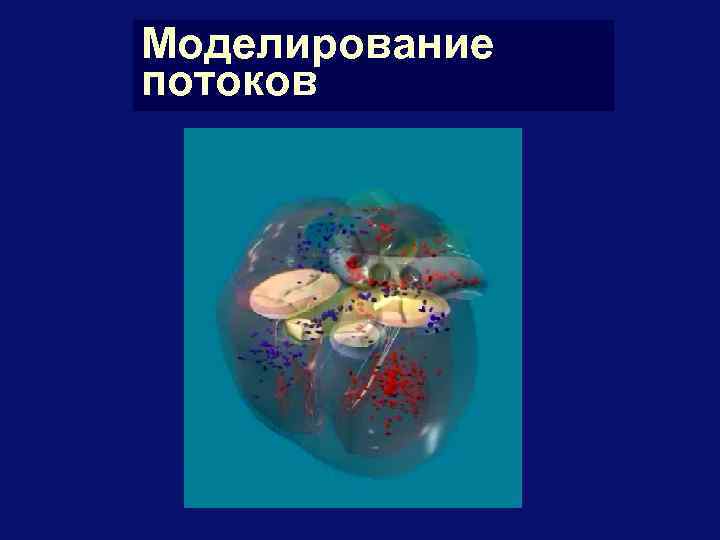

Моделирование потоков